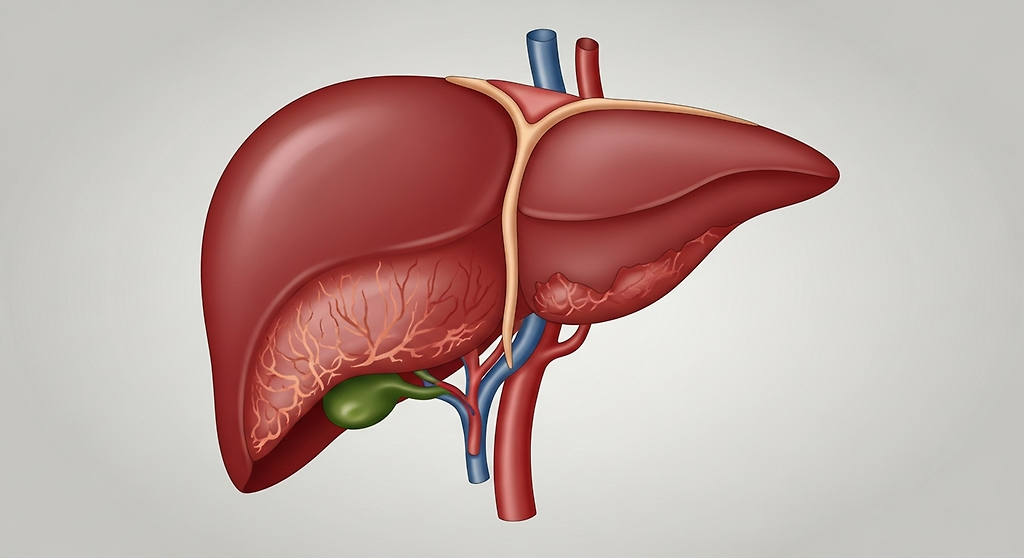

간암은 초기에는 특별한 증상이 없어 조기 발견이 어렵지만, 진행 속도가 빠르고 전이 가능성이 높기 때문에 꾸준한 검진과 관리가 매우 중요합니다. 이번 글에서는 간암 1기, 2기, 3기, 4기 생존율과 간암 말기 증상에 대해 단계별로 살펴보겠습니다.

간암은 일반적으로 병기(1기~4기)에 따라 암의 크기, 혈관 침범 여부, 전이 범위로 구분됩니다. 각 단계마다 치료 가능성과 생존율에 큰 차이가 있습니다.

먼저 간암 1기는 암이 작고 간 내부에만 국한되어 있을 때입니다. 이 시기에는 간 기능이 비교적 잘 유지되어 있고, 수술이나 고주파 절제술 등으로 완치가 가능할 정도입니다. 통계적으로 간암 1기의 5년 생존율은 약 60~70%로 보고되며, 조기 발견 시 예후가 매우 좋습니다.

간암 2기는 암의 크기가 커지거나 여러 개의 결절이 생기기 시작한 단계입니다. 아직 간 외부로 퍼지지는 않았지만, 혈관 침범이 나타날 수 있습니다. 이때는 수술, 간이식, 국소 치료(색전술 등)가 병행될 수 있으며, 5년 생존율은 약 40~50% 정도입니다.

간암 3기는 암이 큰 혈관을 침범하거나 간 주변 림프절로 전이된 상태를 말합니다. 치료가 점차 어려워지고, 간 기능이 저하되기 시작합니다. 항암치료나 표적치료제, 면역항암제 치료가 사용되며, 5년 생존율은 약 10~20% 수준으로 떨어집니다.

간암 4기는 암이 간 외부로 전이된 말기 단계입니다. 폐, 복막, 뼈 등으로 퍼질 수 있으며, 간 기능이 심하게 저하된 상태입니다. 이때는 완치를 기대하기 어렵고, 통증 완화 및 삶의 질을 유지하는 치료가 중심이 됩니다. 간암 4기 생존율은 약 5% 이하로 매우 낮습니다.

간암 말기 증상은 간 기능 저하와 전이로 인해 전신적인 변화가 나타납니다. 대표적인 증상으로는 심한 피로감, 식욕 부진, 체중 감소, 복부 팽만감, 황달, 복수(배에 물이 차는 현상) 등이 있습니다. 피부나 눈이 노래지고, 소변이 진해지며, 가려움증이 심해질 수 있습니다. 복부 통증이나 오른쪽 갈비뼈 아래의 묵직한 느낌도 흔합니다. 암이 폐나 뼈로 전이되면 기침, 호흡곤란, 뼈 통증 같은 증상이 동반될 수 있습니다.

간암은 조기 발견 시 치료 성과가 좋은 편이므로, 정기적인 간 초음파 검사와 혈액검사(알파태아단백 AFP 검사)가 매우 중요합니다. 특히 B형·C형 간염 보유자, 과음하는 사람, 지방간이 있는 사람은 고위험군으로, 주기적인 검진이 필수입니다.

결국 간암 1기~4기 생존율은 병기별로 큰 차이가 있으며, 간암 말기 증상은 간 기능 저하로 인한 전신적 피로와 복수, 황달 등이 특징입니다. 조기 발견과 꾸준한 관리가 간 건강과 생존율 향상의 핵심입니다.